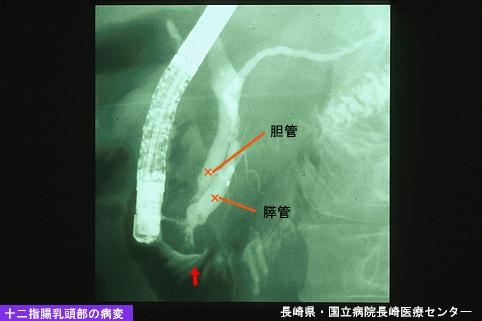

A case of relatively early stage carcinoma of the papilla vater with a gastric stromal tumor (GIST).

Nagasaki Pref., National Hospital Organization Nagasaki Medical Center

Malignant epithelial tumor/Adenocarcinoma

Duodenum/Papilla, ampulla of Vater

X-ray